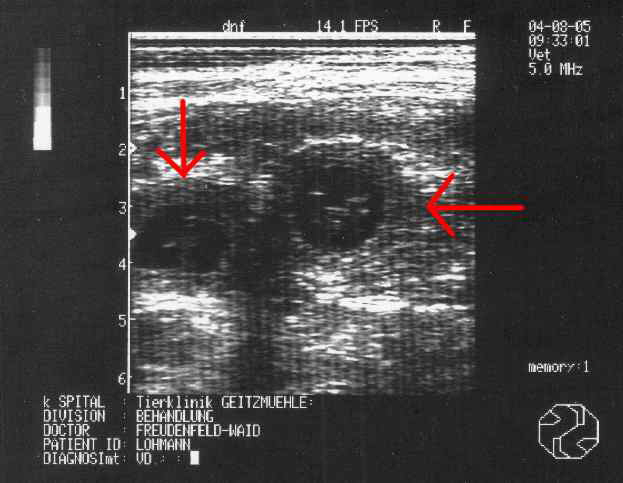

Das Ultraschallbild von Phila in der vierten Woche